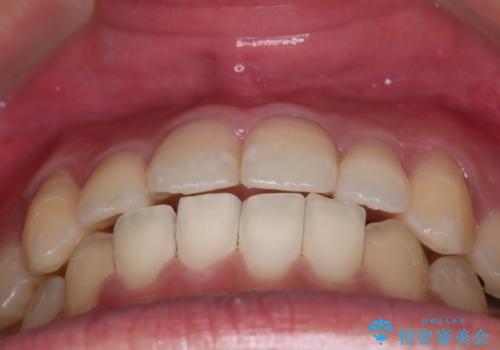

非抜歯矯正だったこともあり、1年半以内という短い期間で矯正を終了することができました。

気にされていた八重歯とがたつきが綺麗に改善されました。